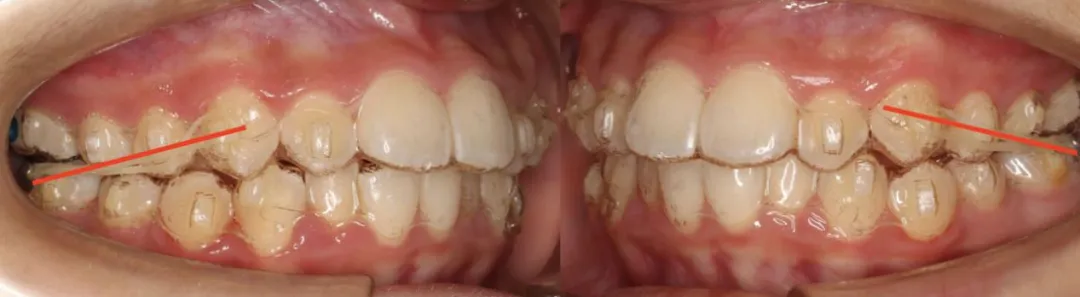

简单地说,Clarks医生认为上下牙齿的咬合斜面,会传导咬合力到牙槽骨,不同的咬合斜面传导到牙槽骨的力的方向不一样。

也就是说I类的咬合斜面,咬合力传导到牙槽骨是I类的刺激牙槽骨改建的力量。II 类的咬合斜面,咬合力传导到牙槽骨是II类的刺激牙槽骨改建的力量。

因此改变II类的咬合斜面,就可以改变刺激颌骨改建的II类力量。给II类的患者带上I类咬合关系的咬合板,在II类患者的口内模拟I类的咬合关系,引导下颌向前,促进下颌生长。